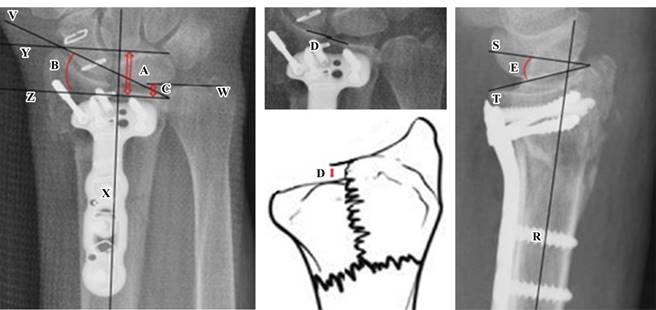

Se estandarizaron dos evaluadores en la técnica de medición radiográfica para reducir errores. Se empleó el software Carestream® que produce mediciones con precisión de centésimas de mm o grado. El primer paso consistió en la correcta identificación del eje anatómico del radio. Para esto, se trazó una línea longitudinal en el centro del radio (X) equidistante de ambas corticales en los dos planos (PA y lateral).

Luego de trazar el eje anatómico en el plano PA, se trazó una línea perpendicular al eje del radio pasando por la cortical de la punta de la estiloides radial (Y) y otra también perpendicular al eje del radio, pero trazada en la porción más cubital de la superficie articular distal (Z). Posteriormente se trazó una línea desde la cortical de la apófisis estiloides hasta el borde cubital del radio distal (V). La última línea en el plano PA fue una perpendicular al eje de radio a nivel de la superficie articular distal del cubito (W).

Luego de trazar el eje longitudinal del radio (R) en el plano lateral, se trazó una línea perpendicular a nivel del borde distal de la cortical dorsal del radio (S). A continuación se trazó una línea para unir los bordes volar y dorsal del radio en el plano lateral (T).

Las mediciones fueron realizadas por dos médicos especialistas en traumatología y ortopedia. La Figura 1 ilustra las mediciones que se emplean para determinar el éxito postquirúrgico radiográfico en las fracturas de radio distal. Se tomaron cinco medidas: 1) altura radial, distancia entre dos líneas perpendiculares al eje del radio (X); la que pasa por la punta de la apófisis estiloides (Y) y la que pasa por la superficie distal del radio en su región más cubital (Z); 2) la inclinación radial describe el ángulo (B) en el plano PA; formado entre la línea perpendicular al eje longitudinal del radio trazada en la porción más cubital de la superficie articular distal (Z) y la línea que une la parte distal de la apófisis estiloides y el borde cubital del radio distal (V); 3) varianza cubital, distancia entre la línea perpendicular al eje longitudinal del radio trazado en la porción más cubital de la superficie articular distal del radio (Z) y otra paralela, pero a nivel de la superficie articular distal del cubito (W); 4) escalón articular, distancia entre cada extremo de la cortical articular distal del radio (D), se describe en una fractura con patrón articular; y 5) inclinación volar, ángulo que se forma de una línea perpendicular (S) al eje del radio (R) que hace contacto con el borde distal de la cortical dorsal del radio y la línea que pasa por los bordes volar y dorsal del radio en el plano lateral (T).

Altura radial (A): distancia entre líneas Y y Z; éxito 10-13 mm, sin éxito < 10 y > 13 mm.

Inclinación radial (B): ángulo entre líneas V y Z; éxito 21-25º, sin éxito < 21 y > 25º.

Varianza cubital (C): distancia entre líneas Z y W; éxito 0 ± 1.5 mm, sin éxito > 1.5 mm.

Escalón articular (D): ángulo entre líneas S y T; normal < 2 mm, sin éxito ≥ 2 mm.

Inclinación volar (E): distancia entre cada extremo de la cortical articular distal del radio; normal 7-15º, sin éxito < 7 y > 15º.